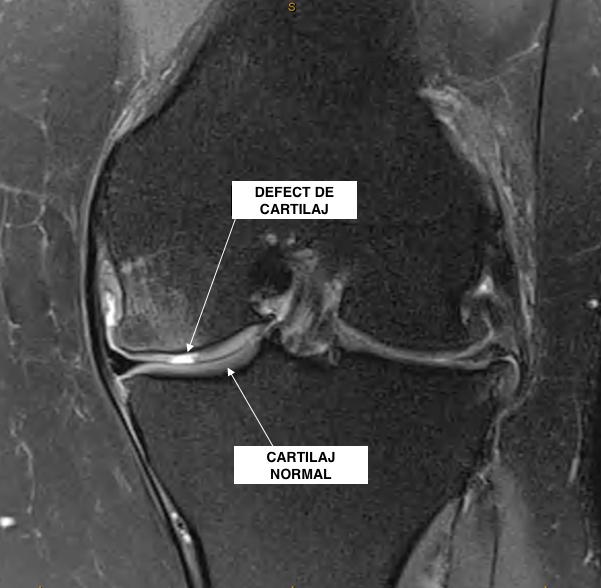

- Radiografie simplă: față și profil, pentru a distinge diminuarea sau dispariția cartilajului;

- Examinare RMN (rezonanță magnetică nucleară): identificarea precisă a leziunilor intraarticulare;

- Artroscopie exploratorie: intervenție chirurgicală minim invazivă, cu vizualizare directă a leziunii.